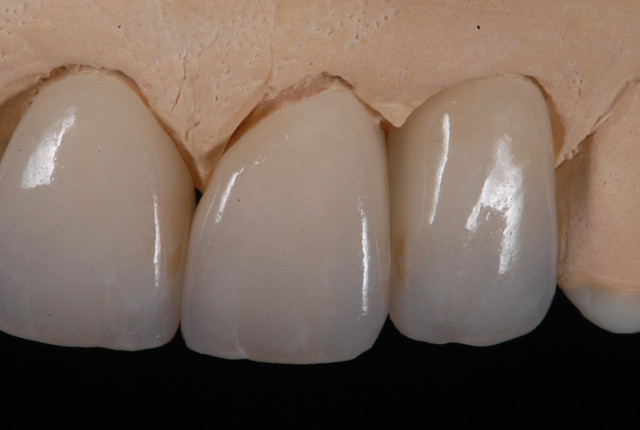

E.max crown try in 280713

#Togias 190713 nora